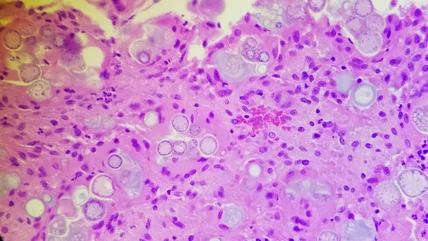

Valley fever results from the inhalation of Coccidioides spores that live in soil and dirt, which generates a lung infection. This can then lead to shortness of breath, fever, chest pain, and fatigue. Approximately 15–30% of community-acquired pneumonia in Phoenix and Tucson is caused by Coccidioides. Although valley fever is the acute form of coccidioidomycosis, it can become even more serious and develop into a chronic illness. People with weak immune systems are at the greatest risk for this ongoing infection.